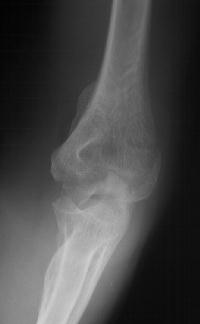

81 year old physically active woman sustained a left elbow fracture in a syncope related fall.

Lateral and central fracture component displacement.

Unusual contour visible at the medial metaphyseal flare.

This is seen on the lateral view to be the anterior half of the central articular surface.